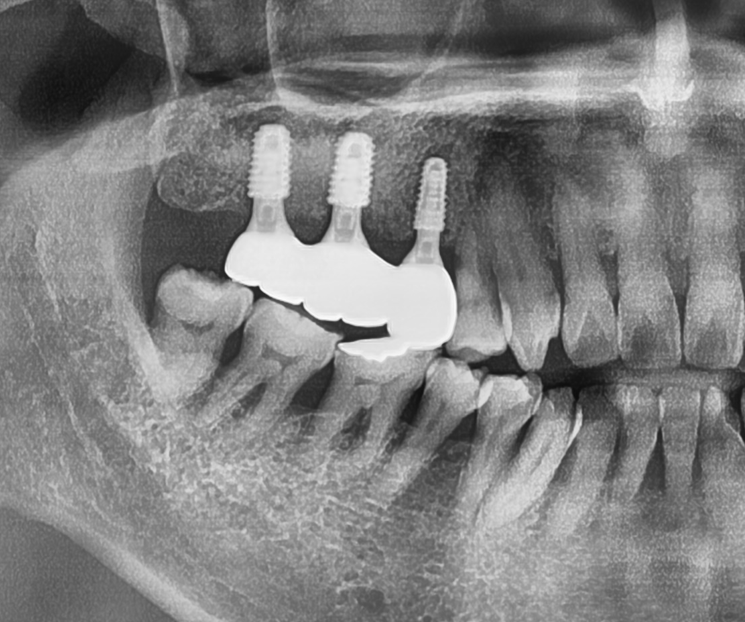

편측으로 먼저 지르코니아 크라운까지 다 올려드린 뒤에 남은 편측을 진행합니다.

시간이 또 대략 2개월 가량이 흘러서 이렇게 지르코니아 크라운까지 시적을 해드리면